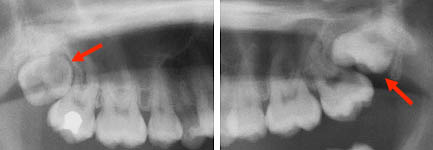

Problèmes d’éruption des troisièmes molaires supérieures. Seule une radiographie peut permettre de déceler cette anomalie (femme de 25 ans). Ces dents ne sortiront pas adéquatement et leur malposition extrême justifie de les extraire. La dent sur la photo de droite peut endommager la deuxième molaire si elle demeure en bouche.